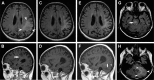

Background: Secondary central nervous system lymphoma (SCNSL) is a rare and aggressive disease, which is defined as secondary central nervous system (CNS) involvement in patients with systemic lymphoma. According to previous reports, SCNSL presents mostly with leptomeningeal spread; however, our experience differs. In the present study, we demonstrate the diversity of magnetic resonance imaging (MRI) patterns in SCNSL.

Patients and methods: Initial morphological MRI findings in 21 patients (10 women and 11 men with mean age 62.3±16.2 years) with SCNSL were retrospectively evaluated. All patients suffered from neurological symptoms and underwent MRI, and all cases were histologically verified. Twelve patients were treated by corticosteroids at the time of the initial MRI.

Results: Parenchymal lesions were present in 18 of 21 cases (85.7%), solitary meningeal infiltration was present in 1 patient (4.8%), leptomeningeal infiltration in combination with hypophyseal involvement in 1 patient (4.8%), and solitary involvement of the sixth cranial nerve (CN) was found in 1 patient (4.8%). Multiple lesions were present in 11 of 21 cases (52.4%). Diffusion restriction in all or part of the lesion was detected in 14 of 18 cases (77.8%). All parenchymal lesions had an infiltrative appearance and most enhanced homogenously (11 of 17 cases; 64.7%). A combination of parenchymal and meningeal involvement was found in 10 of 21 cases (47.6%). Infiltration of the CNs, basal ganglia, corpus callosum, and ependyma was present in 8 of 21 cases (38.1%) for each of the abovementioned structures; hypothalamic-hypophyseal axis was affected in 7 of 21 cases (33.3%).

Conclusion: In contrast to previous reports, SCNSL presented as parenchymal disease. MRI is not sufficient for differentiation between primary and secondary CNS lymphoma.